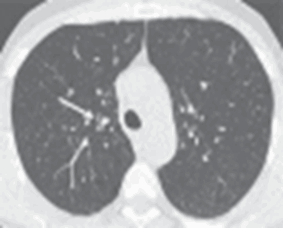

(Слева) На аксиальной КТ с КУ у женщины 37 лет с отеком легких определяется ровное утолщение междольковых перегородок. Отек позволяет различить полигональные границы вторичных легочных долек в базальных отделах легкого. Обратите внимание на хорошо заметные центральные дольковые артерии на фоне утолщения центрилобулярно-го интерстиция.

(Справа) На корональной КТ с КУ у этой же пациентки на периферии средней доли визуализируются вторичные легочные дольки, окруженные толстыми междольковыми перегородками. (Слева) На аксиальной КТ с КУ у мужчины 68 лет с метастатическим раком предстательной железы и лимфотенным канцеро-матозом определяется нодулярное утолщение междольковых пе регородок, незначительный плевральный выпот справа видны также разбросанные мелкие узелки в легких (гематогенные метастазы).

(Справа) На корональной КТ с КУ у этого же пациента определяется нодулярное утолщение междольковых перегородок вокруг многих вторичных легочных долек. Обратите внимание на асимметричный характер поражения с сохранностью некоторых участков, характерный для лимфогенного канцероматоза. (Слева) На аксиальной КТВР у женщины 59 лет с саркоидозом визуализируются сгруппированные перилимфатические микроузелки с обеих сторон на фоне нодулярного утолщения некоторых междольковых перегородок. Некоторые септальные микроузелки очерчивают края вторичных легочных долек.

(Справа) На аксиальной КТВР у женщины 74 лет с интерстициальным легочным фиброзом определяется неравномерное утолщение некоторых междольковых перегородок в сочетании с тракционными бронхо- и бронхиолоэктазами.

(Слева) На аксиальной КТВР у курильщика 45 лет с диспноэ определяются диффузные центрилобулярные участки снижения пневматизации по типу «матового стекла», сопоставимые с респираторным бронхиолитом, ассоциированным с интерстициаль ным заболеванием легких. Тонкая «полоска» сохранной ткани легкого в субплевральных отделах сопоставима с центрилобулярной локализацией изменений.

(Справа) На аксиальной КТ с КУ (,MIP) у женщины 34 лет с инфекционным бронхиолитом визуализируются очаги в виде «дерева в почках», расположенные в центральных отделах вторичных легочных долек, окруженных неизмененной легочной паренхимой. (Слева) На аксиальной КТВР у мужчины-курильщика 58 лет определяются признаки центри-лобулярной эмфиземы в виде множественных участков повышения пневматизации с дольковыми артериями в центре, выглядящими как точки.

(Справа) На аксиальной КТ без КУ у женщины 46 лет с пневмонией, вызванной золотистым стафилококком, визуализируются множественные очаги повышенной плотности по типу «матового стекла» и консолидации. Картина характерна для бронхопневмонии. (Слева) На аксиальной КТВР у фермера с гиперчувствительным пневмонитом определяется т.н. симптом «зельца», проявляющийся повышением пневматизации одних легочных долек (за счет воздушных «ловушек») и снижением пневматизации других долек по типу «матовою стекла» на фоне неизмененной легочной паренхимы.

(Справа) На аксиальной КТ без КУ у женщины 24 лет с организующейся пневмонией визуализируются характерные участки консолидации на периферии легочных долек. Определяются также симптомы обратного гало и атолла. Относительно сохранные вторичные легочные дольки окружены зонами консолидации.